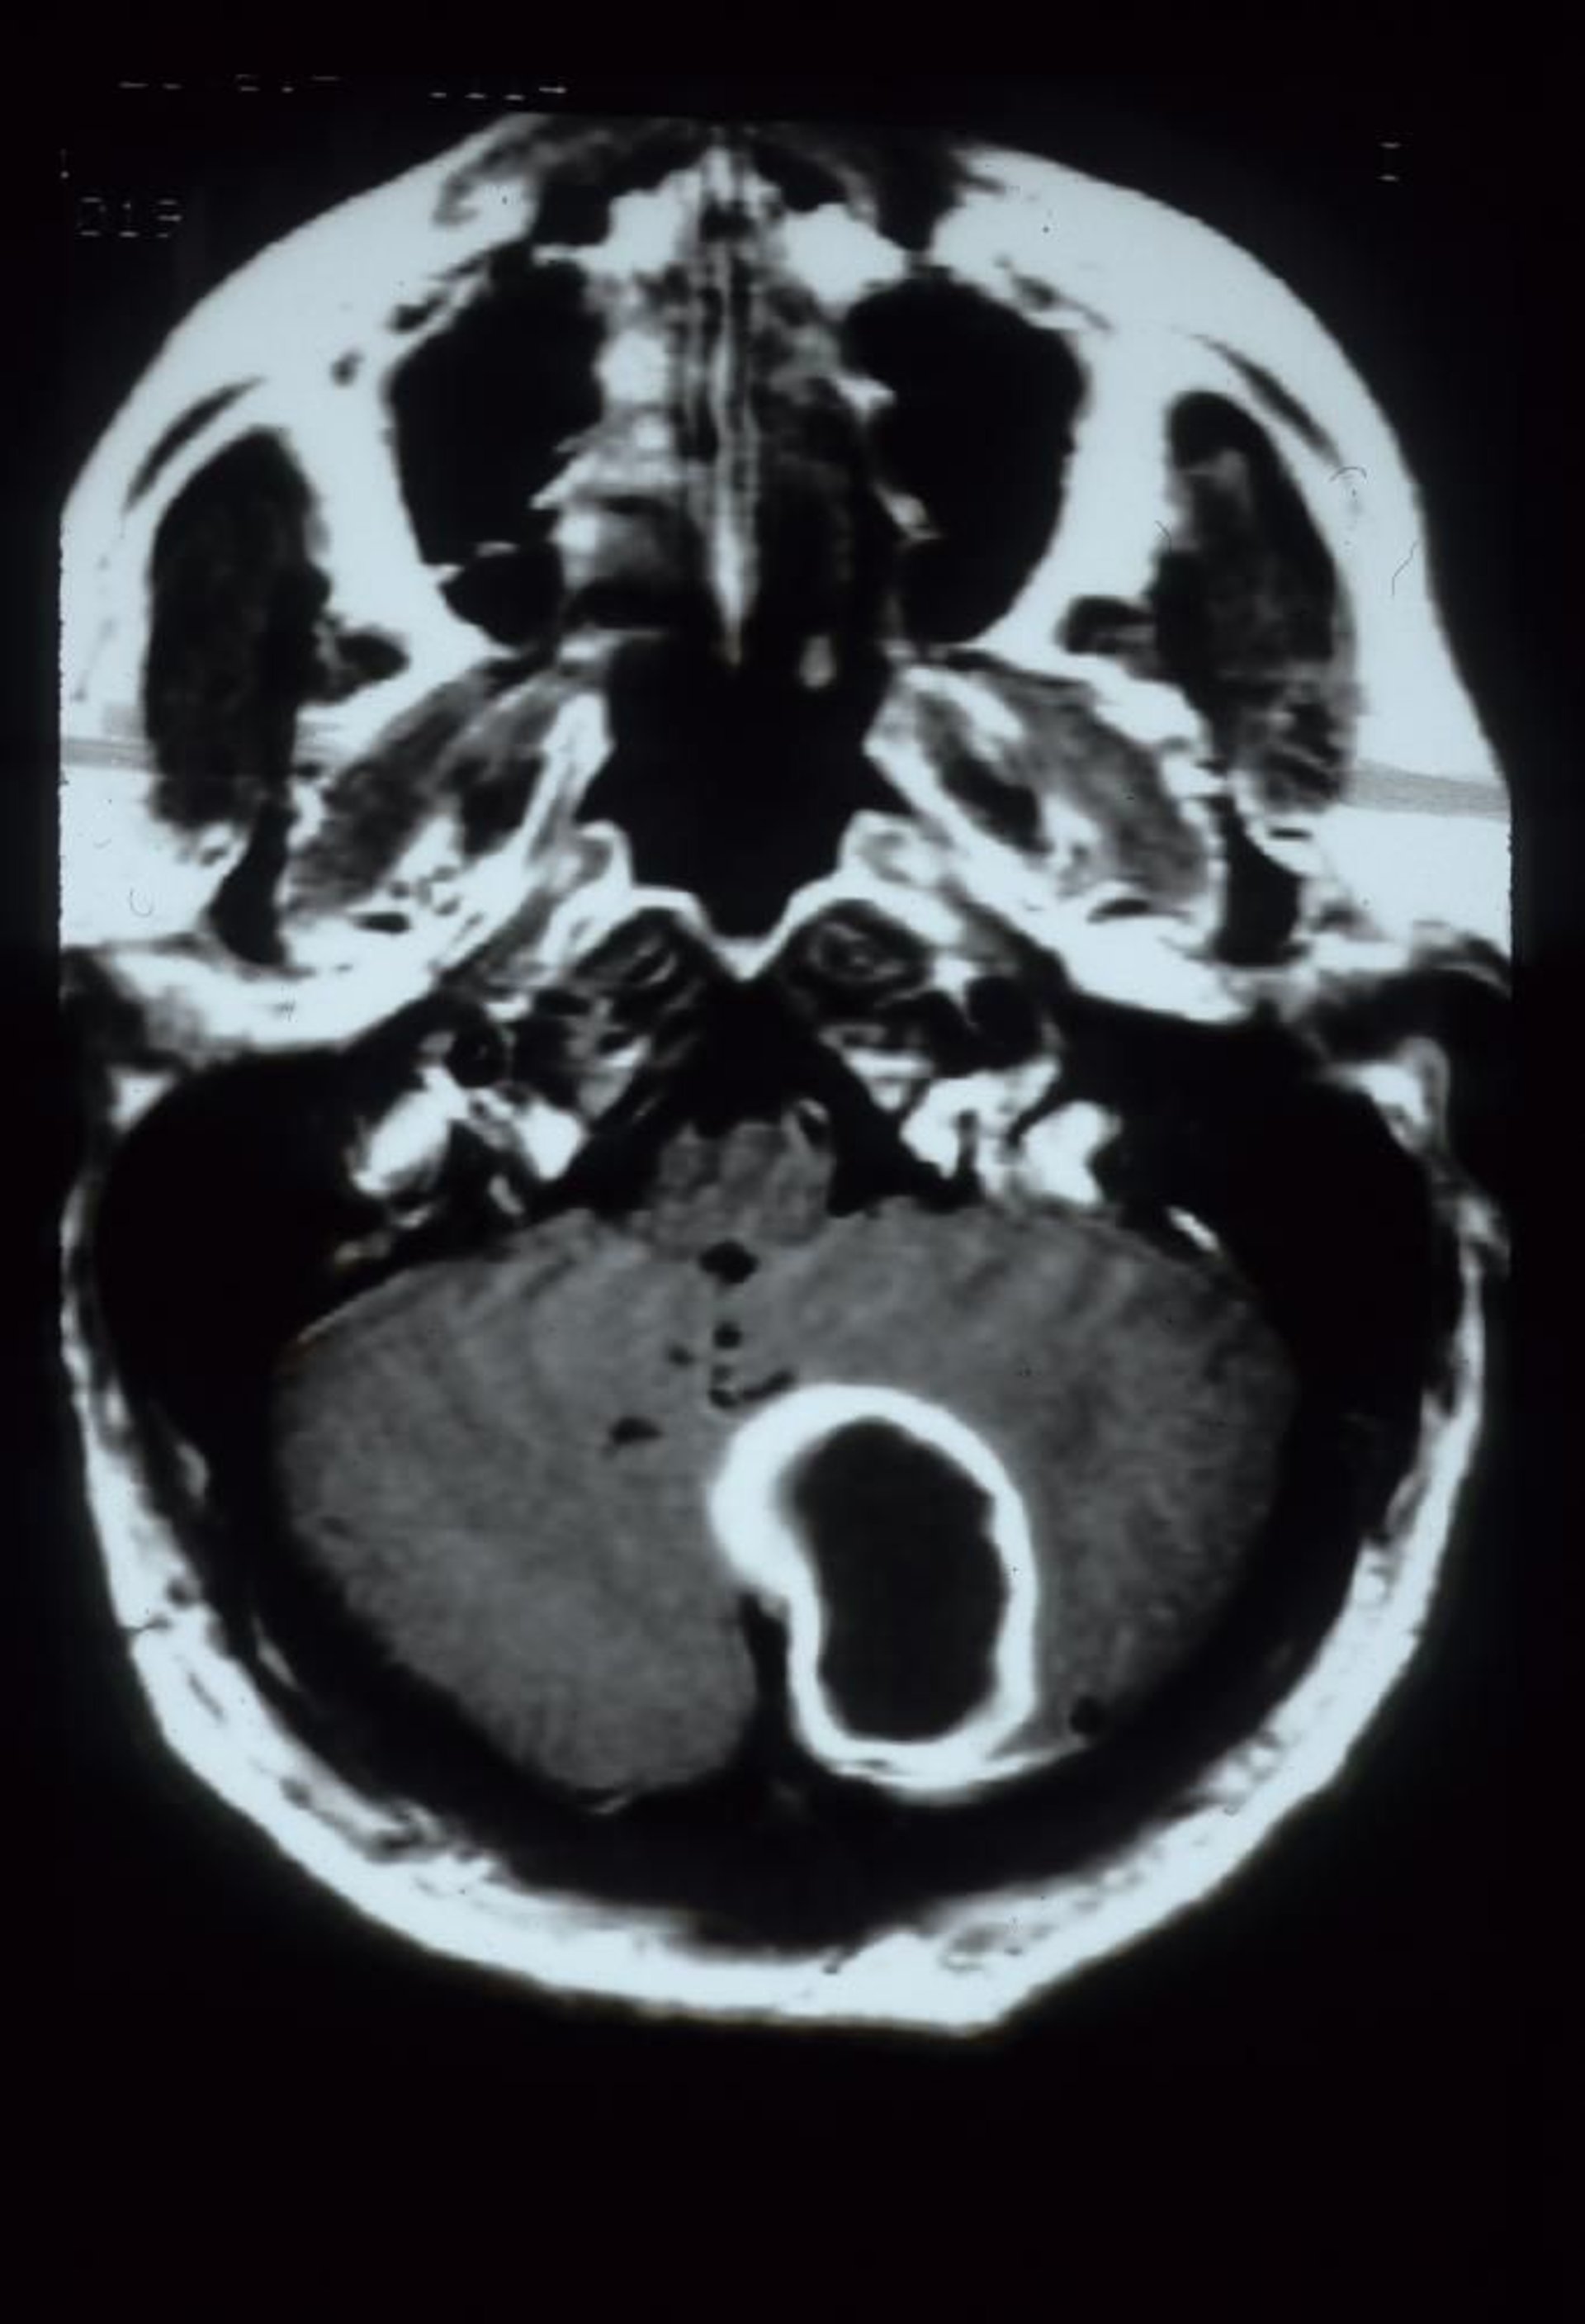

小脳膿瘍

このガドリニウム造影MRI画像では,小脳膿瘍が左小脳半球にリング状の増強効果を示す大きな空洞性病変として認められる。

Courtesy of John E.Greenlee, MD.